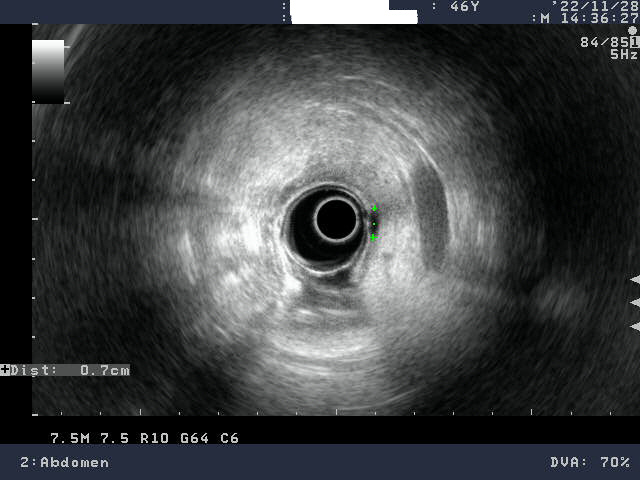

위는 여러개의 층으로 이루어지는데 제일 안쪽면 즉 음식물을 담고 있는 층이 위점막층이고 이 층에서 종양이 생기면 위암이라고 한다. 다행히(?) 나는 그 아래에(점막 밑에) 종양이 1cm 정도 크기로 발견된 것이다. 점막 밑에 있다고 해서 이를 점막하종양이라고 한단다.

병원에서는 크게 걱정할 필요없다고 하지만 보다 정확한 검사를 위해서는 EUS(Endoscopic ultrasound scopy 초음파내시경)라는 검사를 해야 하니까 큰 병원 가보라고 했다. 자기네 병원은 해당 장비가 없어서 검사가 안된다고 했다. 종합병원인데도 없다니 이 장비가 비싸서 그런지.. 다룰 수 있는 의사가 없어서 그런지.. 나중에 안 사실이지만 이 장비를 갖춘 어지간한 병원은 없다고 한다.

당장 내가 사는 광주에서 최고라는 전남대학교병원을 가보고 싶었지만 예약과 검사, 진료의 과정에 시간도 많이 걸릴거 같고 겁도 나고 무서워서 바로 못가봤다. 무엇보다 오래기다려야 하는 대학병원 특성상 당장 이 종양을 제대로 알고 싶어서 급히 광주에서 EUS가 가능한 병원을 폭풍 검색하고 이전에 위내시경을 한번 받아본 적이 있던 서광병원이라는 곳에서 검사가 가능하다기에 바로 예약하고 다음날 검사를 했다. 서광병원에서의 EUS결과로는 0.7cm의 크기.